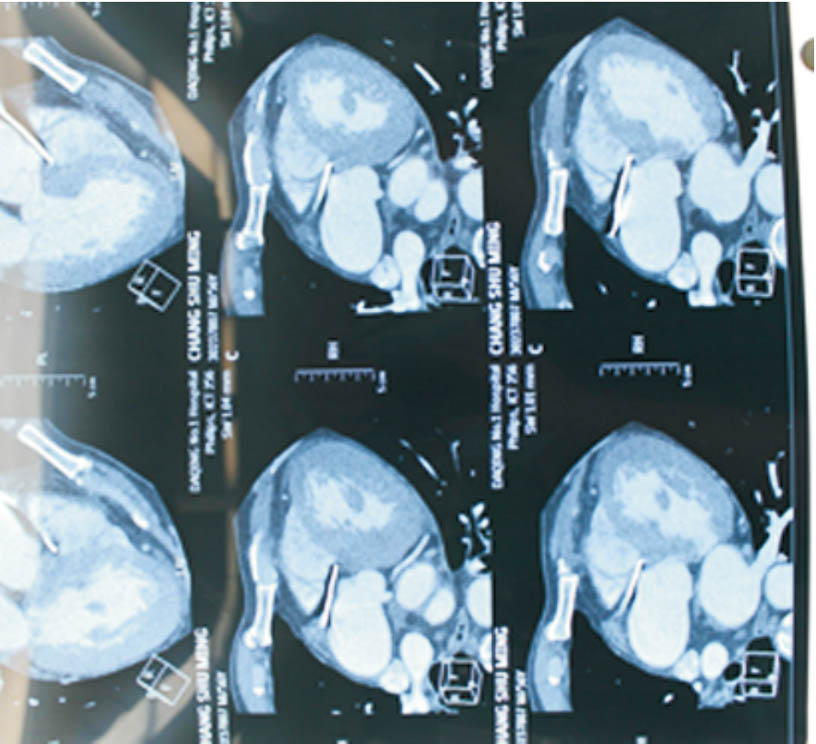

1 资料与方法患者男性,56岁。因间断活动后胸闷痛10余天入院。既往否认高血压、糖尿病,有长期吸烟史。患者近10余天于快速行走及劳累时出现心前区闷痛,无放散痛,无晕厥,休息后胸痛可自行缓解,近2天活动时胸痛频繁发作,且胸痛程度加重。本院门诊行超声心动图示左房38 mm,EF值66%,左室饱满,左室壁增厚,升主动脉稍宽,左室松弛性下降,门诊以“冠心病”收入院。入院查体:T 36.2 ℃,血压 159/84 mmHg(1 mmHg=0.133 kPa),一般状态尚可,呼吸平稳,口唇无发绀,胸壁皮肤无损伤,双肺未闻及啰音。心率62次/min,律齐,未闻及杂音。心电图示心率78 次/min,RV5>2.5 mV,心肌肥厚劳损;急诊肌钙蛋白I测定正常;急诊心肌酶CK-MB正常。入院初步诊断:急性冠脉综合征。入院第3天行冠脉造影示左右冠脉血管未见狭窄病变,透视下可见心包前壁一长约40 mm疑似金属条样物(图 1)。后行胸部CT血管三维成像见升主动脉前方可见条形高密度影,周围可见放射状伪影,长约5 cm,病变自右上至左下走行,于主动脉根部同右心室璧界限不清(图 2)。诊断:心脏异物。停用所有抗血栓药物,并转入我院胸外科治疗,转入胸外科1周后,在全麻下行“心脏异物清除术”,术中于主动脉根部前间壁、右冠开口旁2 cm,可见一长约0.5 cm金属条索样异物,通过主肺动脉窗刺入右心室流出道前壁心肌内,心表面无震颤,围绕异物刺入点,用4-0 prolene 线加垫片荷包缝合两圈,缓慢拔出金属异物,金属异物在心肌内长度约5.5 cm,测量金属条索样异物长度约6.0 cm,刺入点无出血,结扎荷包线(图 3)。术后诊断:心脏异物(金属丝)。追问病史,患者业余爱好舞鞭,该铁丝正是入院前10余天舞鞭时丢失的鞭子头端铁丝(鞭子梢)。术后手术切口愈合良好,术后第6天办理出院。

| 图 2 患者胸部CT血管三维成像结果 |